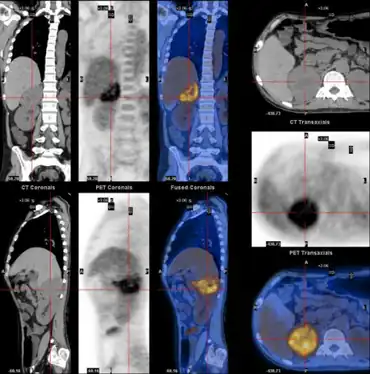

| WDHA caused by pheochromocytoma-,PET-CT scan demonstrating well defined adrenal mass | |